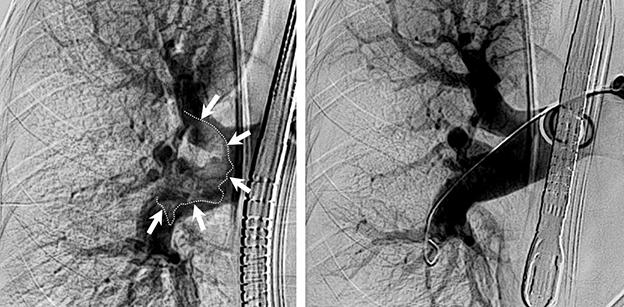

Im Bild: Lunge mit großem Blutgerinnsel (markiert) und dementsprechend mangelnder Durchblutung (links) und nach Entfernung des Gerinnsels und guter Durchblutung (rechts).

Erstmalig in Österreich und erst das vierte Mal in Europa, wurde bei einer Patientin am 19. März an der Innsbrucker Univ.-Klinik für Radiologie, eine Lungenembolie mit einem völlig neuartigen mechanischen System entfernt. Der Patientin geht es gut, sie liegt mittlerweile auf der Normalstation.

„Bei dem kürzlich angewandten System wird ein relativ dicker Schlauch über einen Schnitt in der Leiste, durch ein großes Blutgefäß und das Herz bis in die Lunge vorgeschoben und das Gerinnsel restlos abgesaugt“, erklärt Martin Freund, Geschäftsführender Oberarzt an der Radiologie. „Es ist auch für uns beeindruckend, wie schnell bei diesem Eingriff ein Erfolg zu sehen ist“, sagt Alexander Loizides, Oberarzt an der Radiologie, der den Eingriff gemeinsam mit Freund durchgeführt hat. „Die Werte der Patientin verbesserten sich in der Sekunde in der das Gerinnsel abgesaugt war.“

Die größte Neuerung bei diesem System ist das große Volumen des Schlauches. Bisherige Systeme zur manuellen Entfernung von Blutgerinnseln in der Lunge sind nur ein Drittel so dick und hätten im aktuellen Fall nicht zum Erfolg geführt.